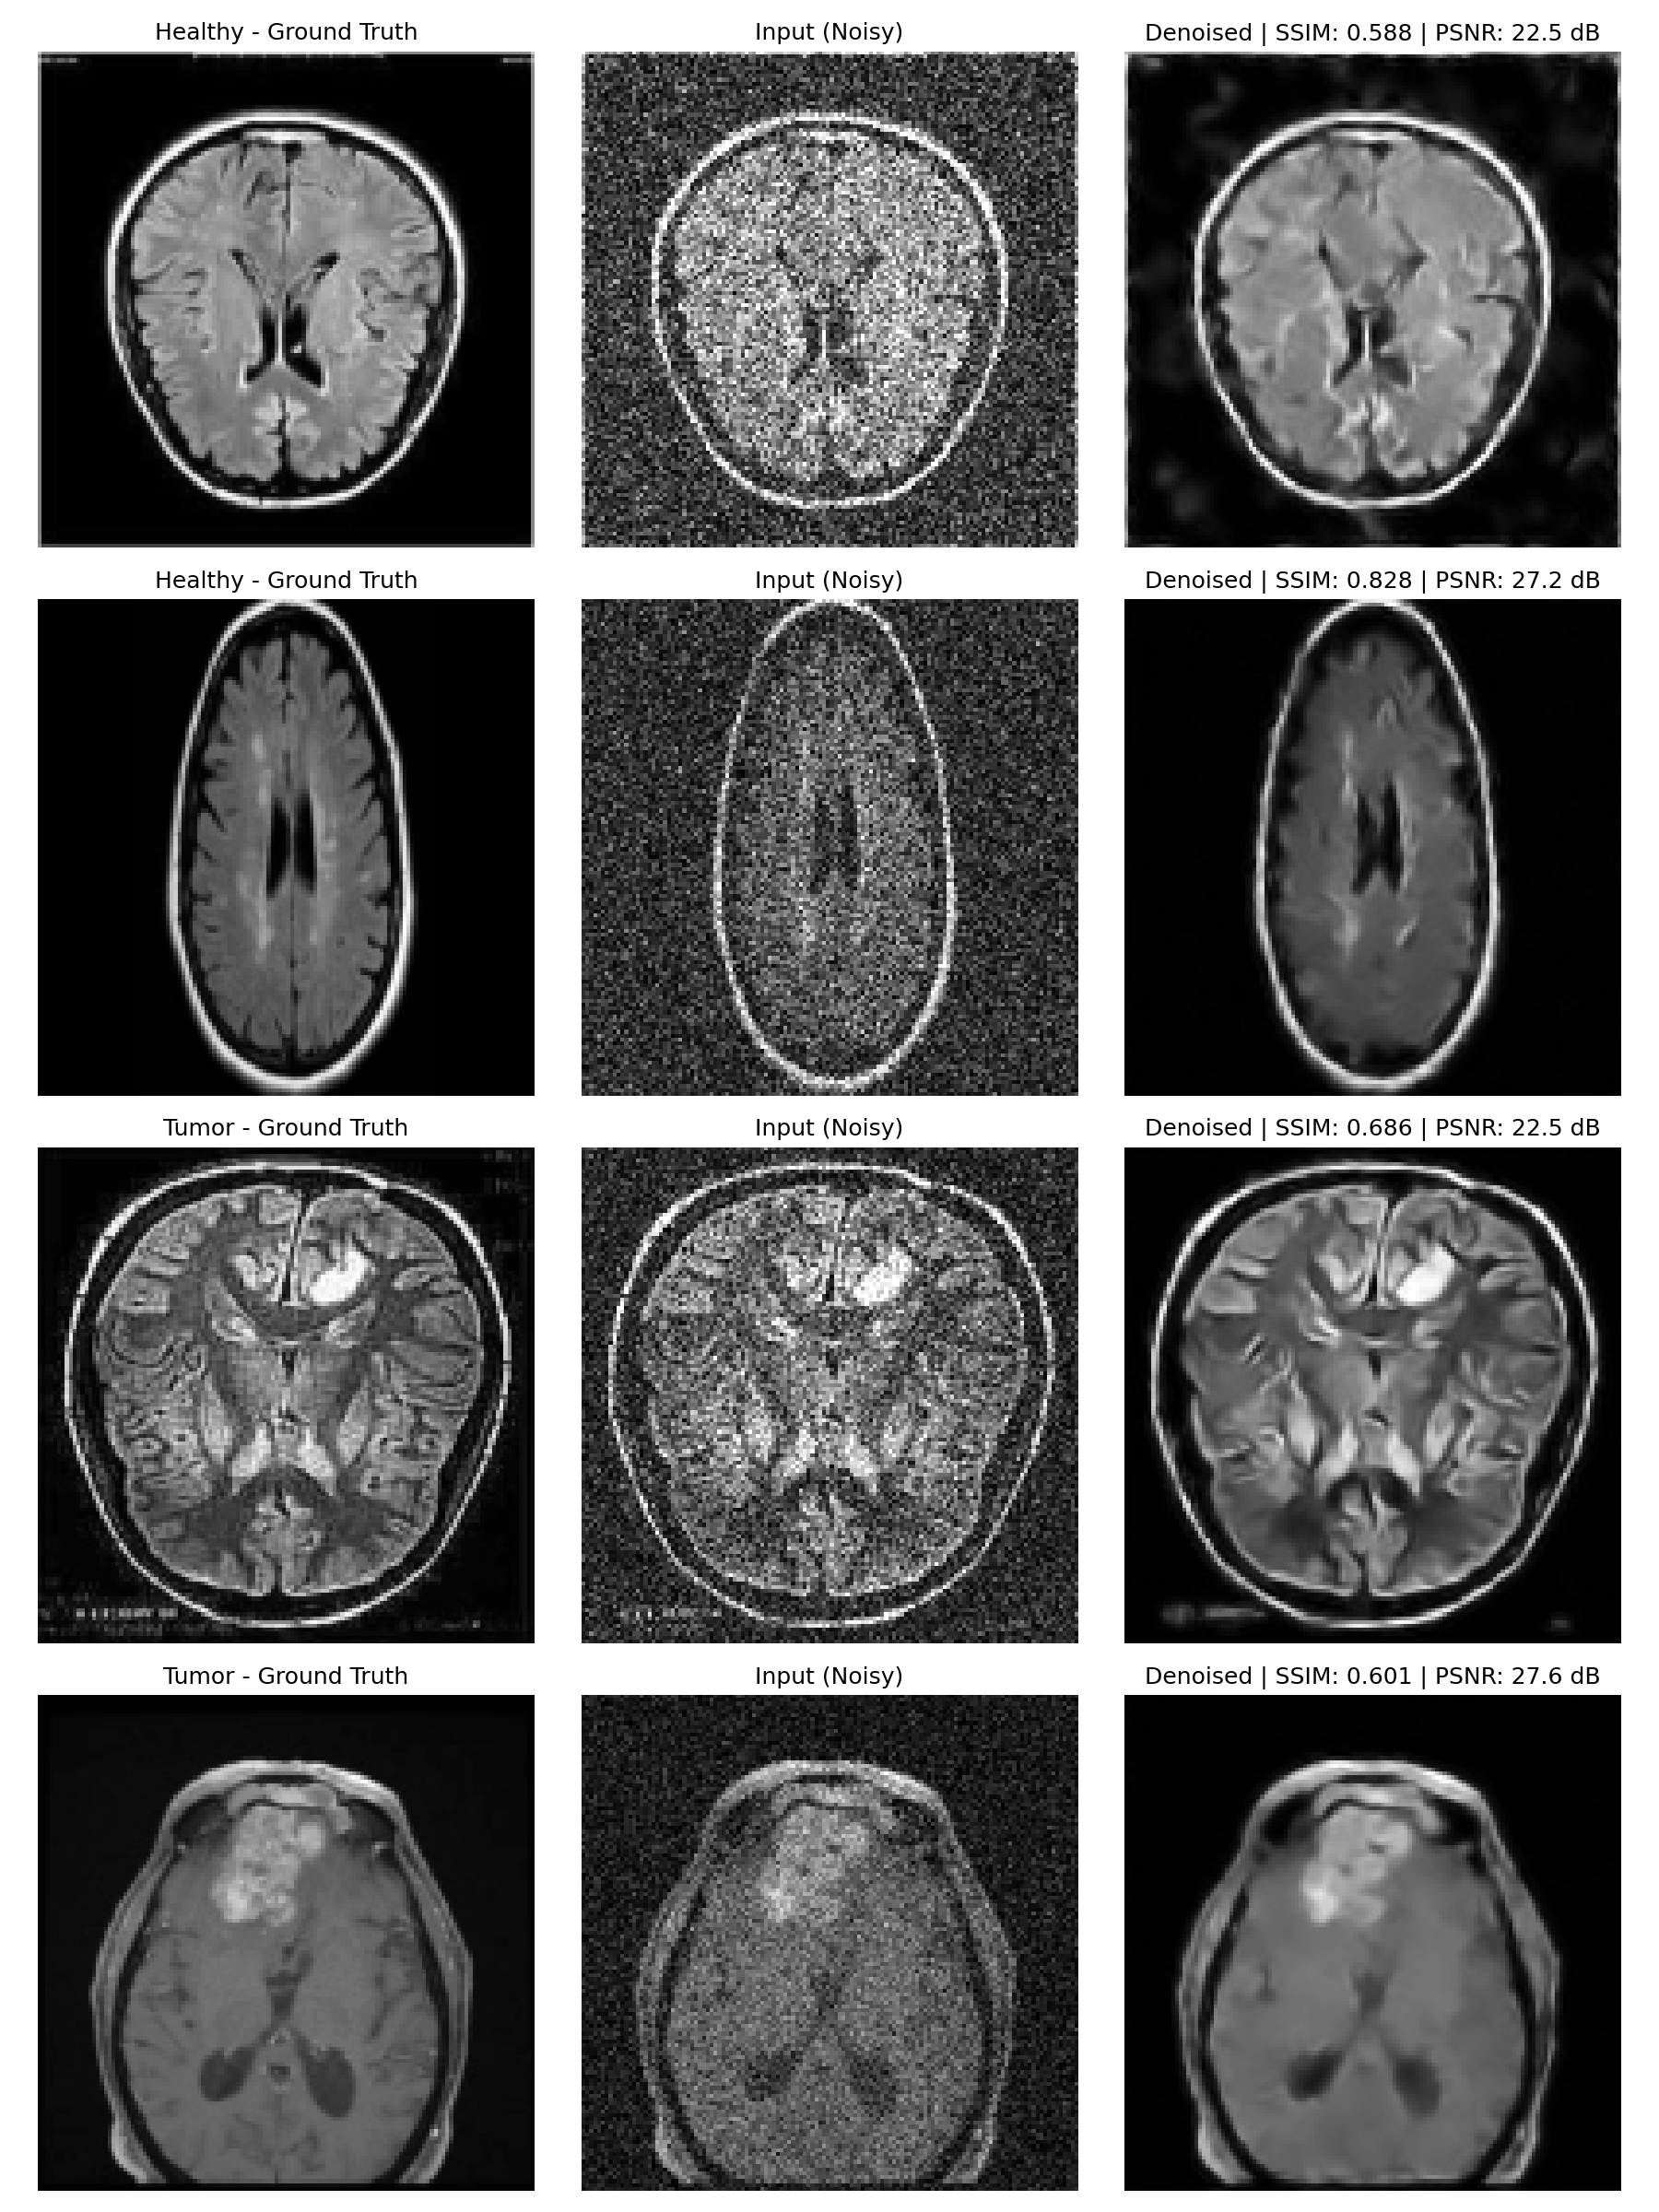

Qualitative MRI denoising examples

Representative clean, noisy, and denoised MRI slices.